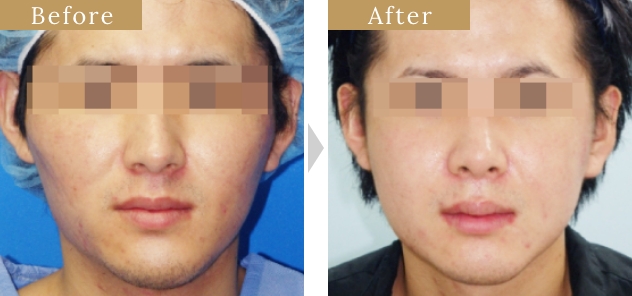

各部位の施術・症例紹介

症例

症例

症例